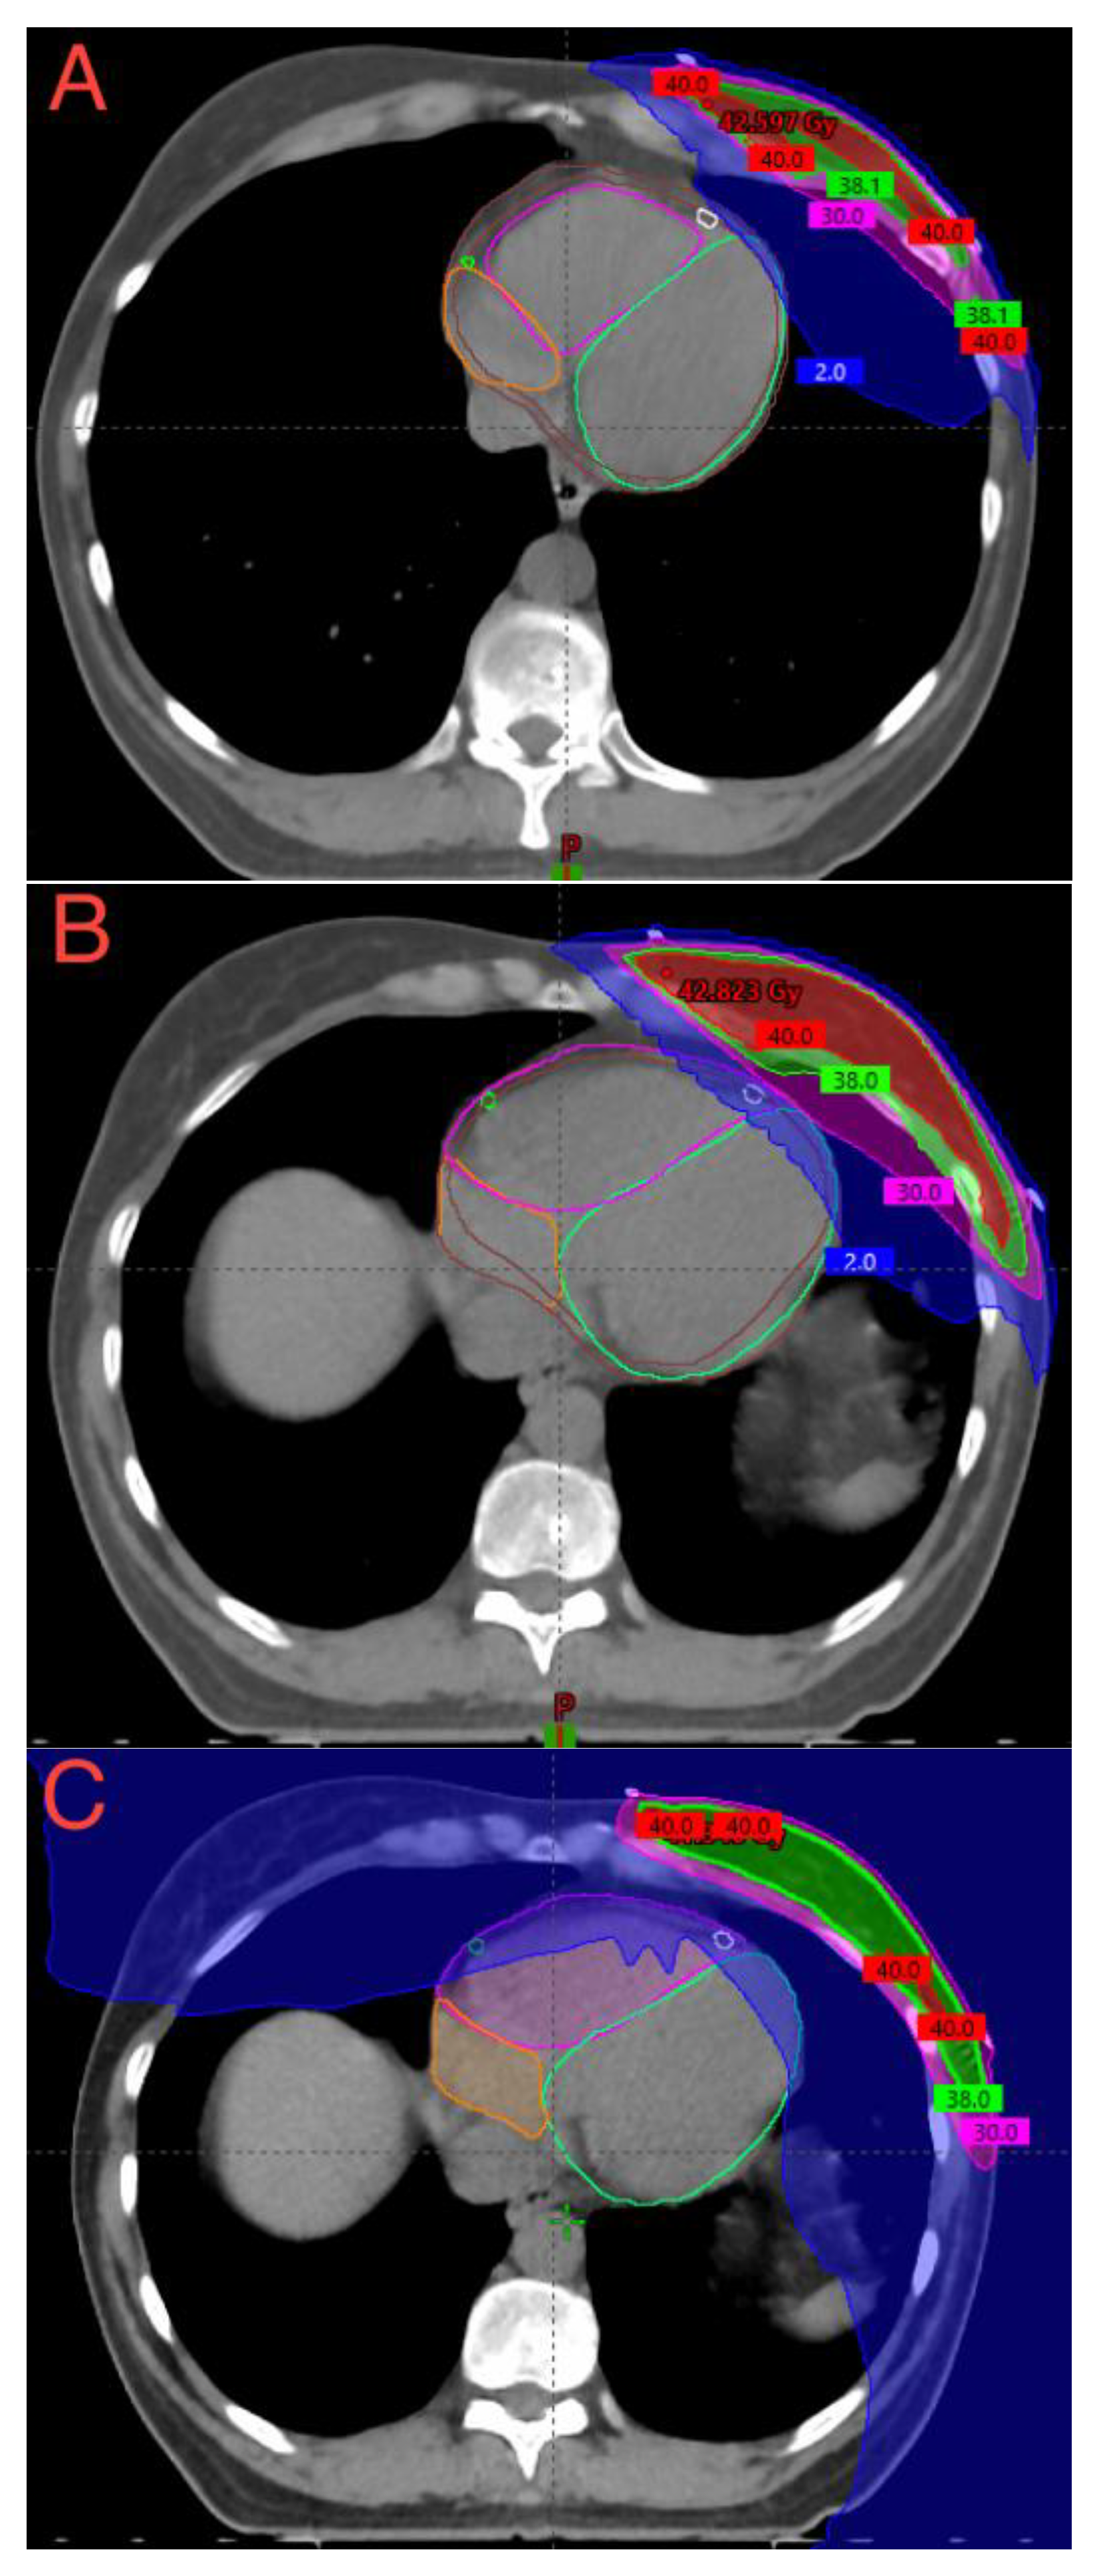

2.3. DIBH-3DCRT and FB-3DCRT Treatment Planning

2.4. FB-HT Treatment Planning